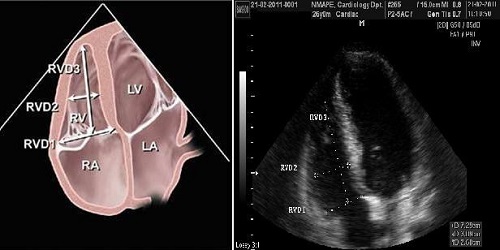

Кількісну оцінку ПШ також найкраще виконувати в апікальній 4-камерній позиції. При цьому треба намагатися вивести справжній нескорочений вид порожнини ПШ в апікальній 4-камерній позиції для отримання максимального поперечного діаметру ПШ. Простим методом кількісної оцінки розміру ПШ є визначення поперечних діаметрів ПШ на рівні середини та базального відділу ПШ (Рис. 11). Крім того, в цій позиції можна також виміряти повздовжній розмір П. В таб. 7 наведені нормальні розміри ПШ в апікальній 4-камерній позиції. На відміну від попередніх рекомендацій [76,80,83], останні рекомендації ASE з ехокардіографічної оцінки правих відділів серця у дорослих 2010 р. [84] не встановлюють меж легкого, помірного та важкого відхилення правих відділів серця від норми, а наводять лише нормативні значення, пропонуючи всі значення вище верхньої межі норми вважати патологічними.

Рис. 11. Визначення поперечних (базального та серединного на рівні папілярних м'язів ЛШ) та повздовжнього розмірів ПШ в апікальній 4-камерній позиції (RVD1 – базальний поперечний розмір ПШ; RVD2 – серединний поперечний розмір ПШ; RVD3 – повздовжній розмір ПШ).